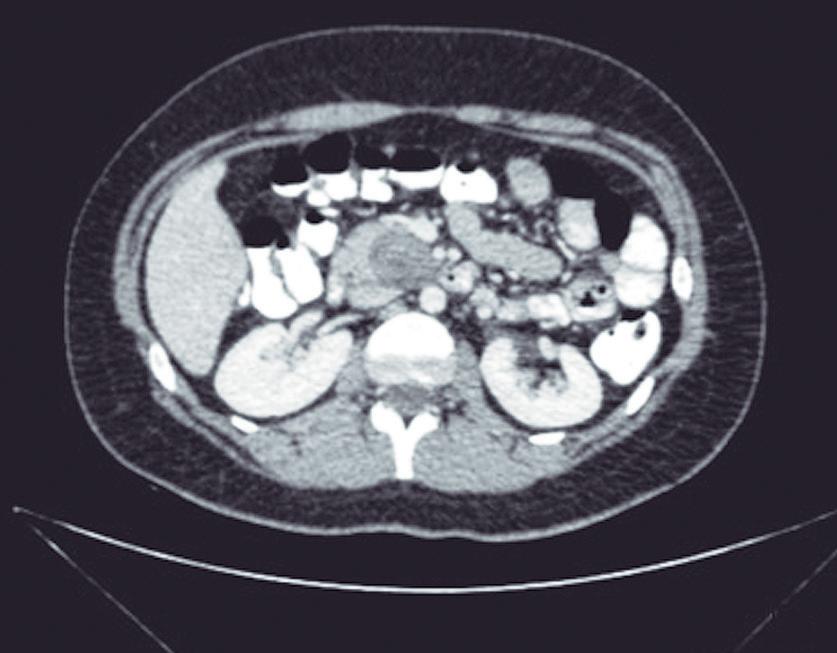

Evaluación de un paciente con dolor epigástrico y hallazgos sincrónicos infrecuentes

Roy López Grove, Daniela Soloaga, Juan Carlos Spina

Roy López Grove, Daniela Soloaga, Juan Carlos Spina 398